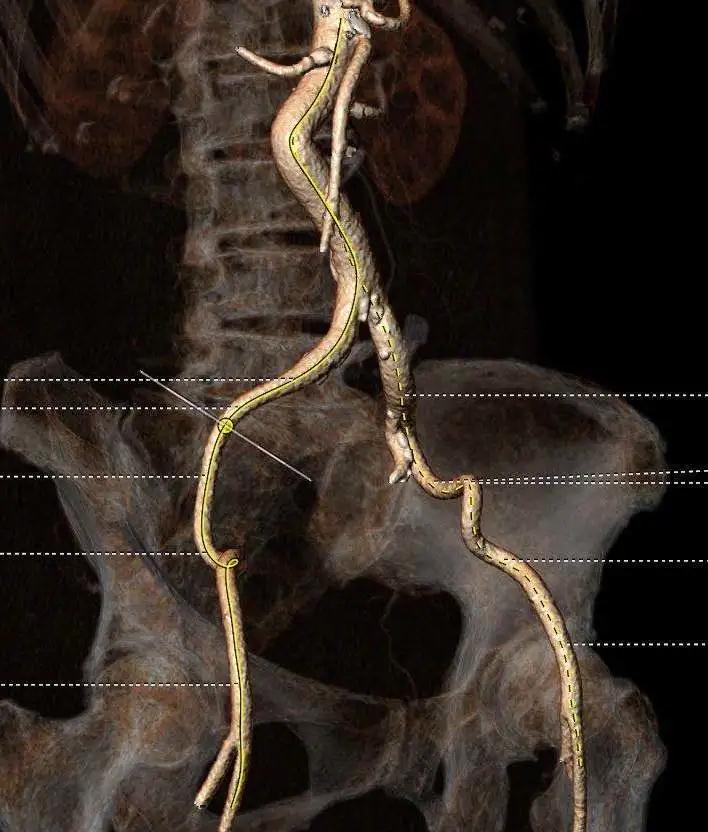

典型病例2

手术演示结束后,线上各位专家针对TaurusElite®瓣膜又进行了深入的讨论。TaurusElite®可回收设计为操作进一步提升了信心,为手术成功提升了保障。可以通过术中的调整可以非常容易的实现瓣膜精准植入,获得最佳的临床结果。同时兼有优异的过弓性能和内联鞘创新设计,更加适合于临床外周血管入路有挑战的患者。

本次结构周转播手术难度较高,周玉杰副院长,张海波教授、刘巍教授通过超高的跨瓣技巧和精准定位释放,再次展现了首都医科大学附属北京安贞医院多学科交叉团队在处理危重复杂病人中的丰富经验,为广大线上观摩专家呈现了多台具有教育指导意义的TAVR病例,并且荣膺本届中国结构性心脏病周“最具贡献奖”。同时,周玉杰副院长也将TAVR患者PCI策略的安贞经验与与会专家分享。